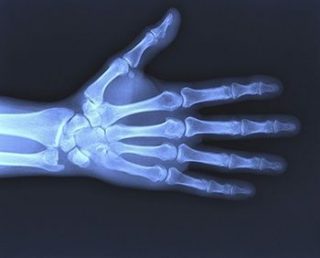

Диагностика повреждения

Основной метод диагностики — рентген.

За симптомами ушибов могут скрываться трещины, вывихи и переломы костей. Если помимо синяка наблюдаются кровоподтеки, отечность и острая боль, необходимо обратиться к врачу.

При сильных ушибах могут назначить УЗИ и МРТ для исключения серьезных повреждений мягких тканей.

Чаще всего врач осматривает руку и назначает рентген для выявления повреждений твердых тканей. Обычно этого достаточно для точной диагностики. Затем определяют тактику лечения в зависимости от степени повреждения.